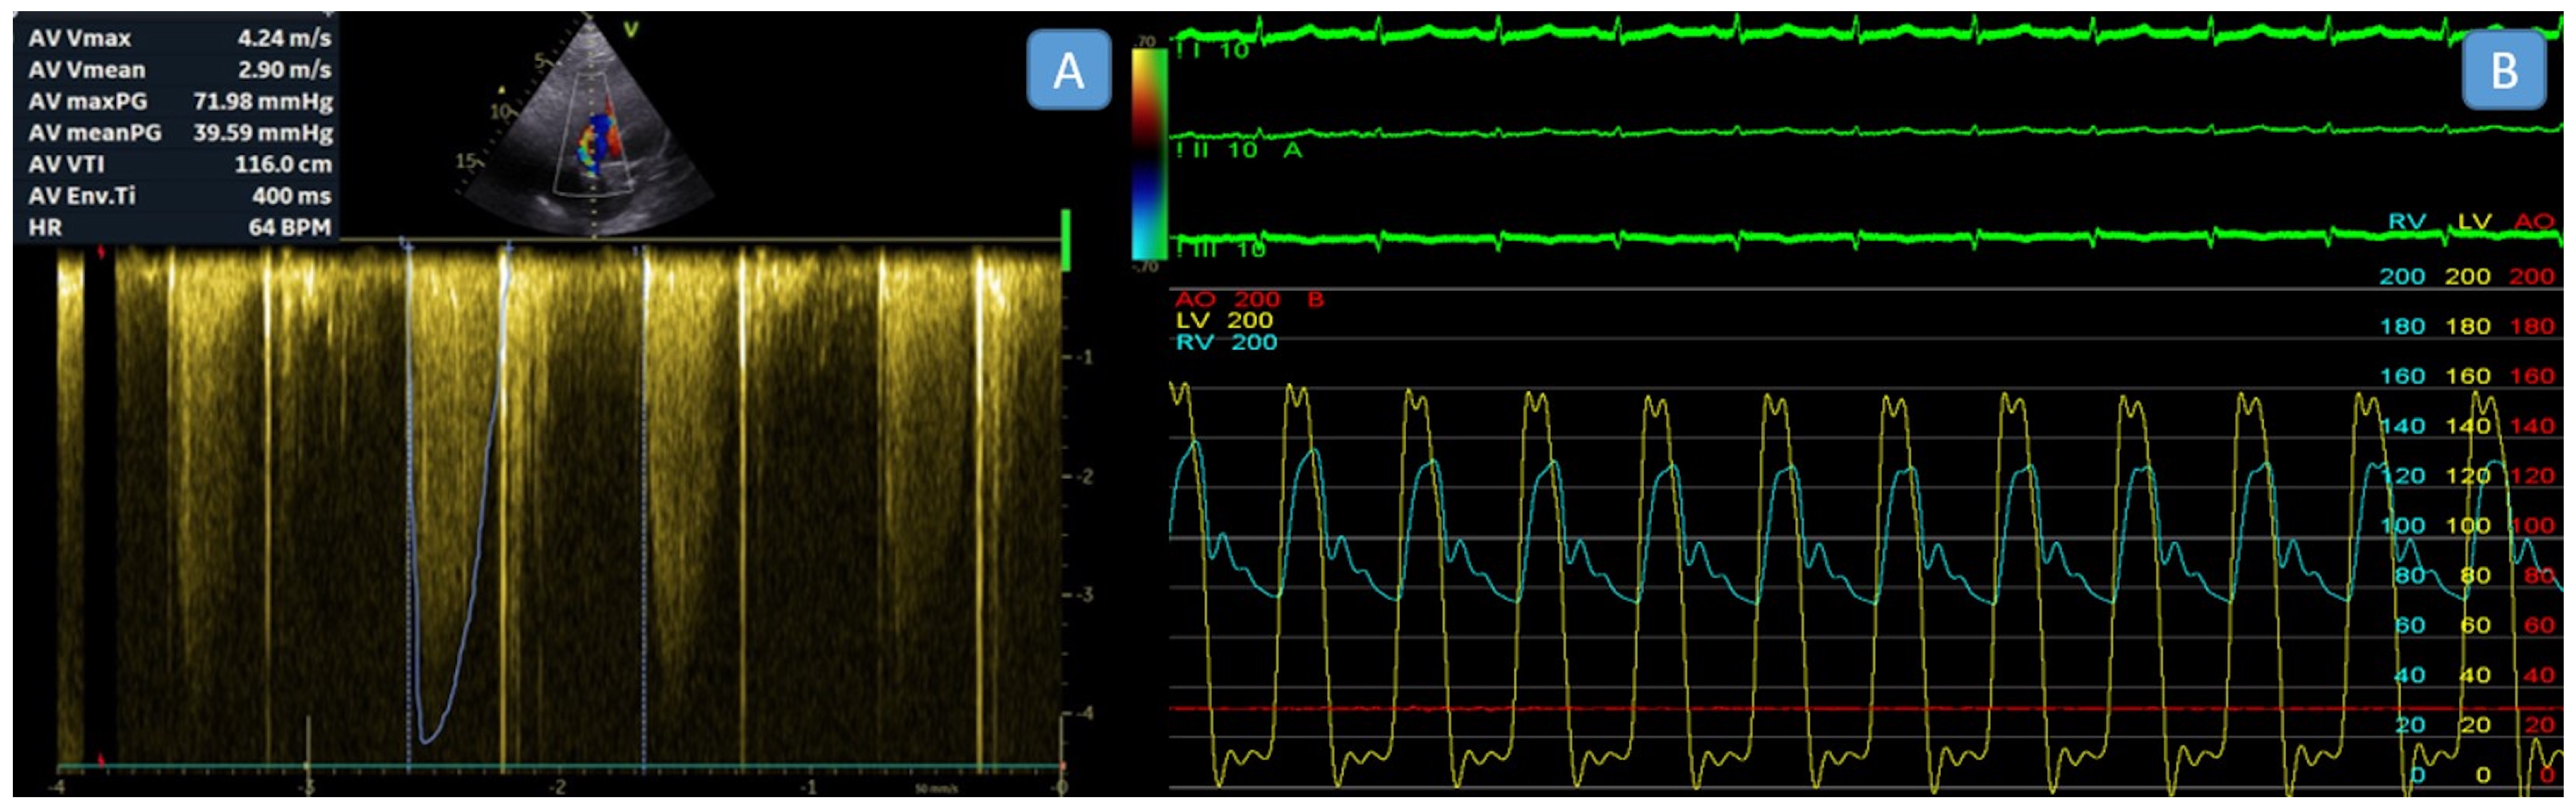

| Invasive transaortic peak-to-peak gradient, mmHg | 47.5 ± 21.74 |